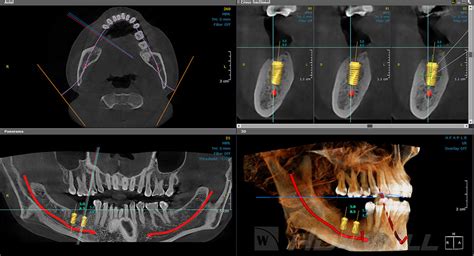

Un TAC dental, también conocido como tomografía computarizada de haz cónico (CBCT), es una técnica de radiografía tridimensional que permite obtener imágenes detalladas de los dientes, los huesos maxilares y las estructuras circundantes. A diferencia de las radiografías convencionales, el TAC dental ofrece una visión en 3D que facilita el diagnóstico y la planificación de tratamientos complejos.

- Planificación de implantes dentales: Antes de proceder a la colocación de uno o varios implantes dentales, necesitaremos saber si tu mandíbula cuenta con la cantidad y densidad suficiente de hueso como para darle soporte.

Es importante diferenciar el TAC dental de la ortopantomografía, también conocida como radiografía panorámica. Mientras que la ortopantomografía ofrece una imagen plana en dos dimensiones, el TAC dental proporciona una imagen tridimensional más precisa y detallada.

En la ortopantomografía se ve una imagen plana, no se ve el volumen. Vemos a lo alto y a lo ancho pero no el grosor. Tiene la desventaja en relación con el Tac 3d, que se una radiografía de dos dimensiones, todo lo vemos aplanado. Para algunos tratamientos, como implantes dentales, hoy día es una temeridad poner un implante dental si tener un tac. El implante tiene que ir dentro del hueso, puede ser que haya altura para colocarlo, pero quizás es un hueso muy fino y el implante no “cabe” en ese grosor.